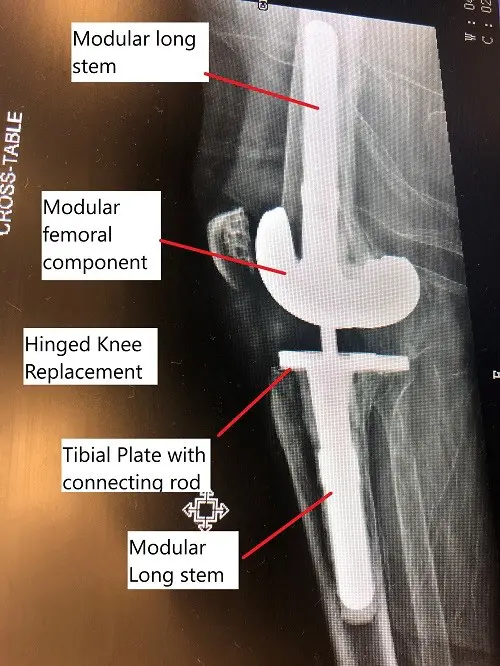

Intraoperative fluoroscopic image showing modular revision knee replacement.

- Revision Surgery: Revision TKR involves replacing or adjusting the existing prosthetic components. Special implants, such as hinged implants or those with rotating platforms, may be used to address instability.